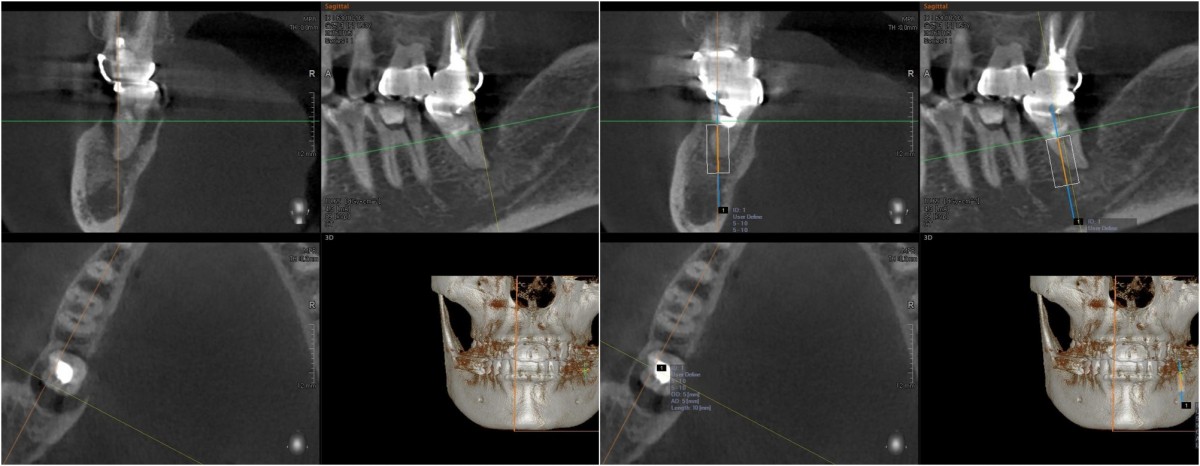

SIngle Implant - Immediate Placement, 8-year follow up

<CJ SBN> old female had mobility and pain when chewing in the lower molar